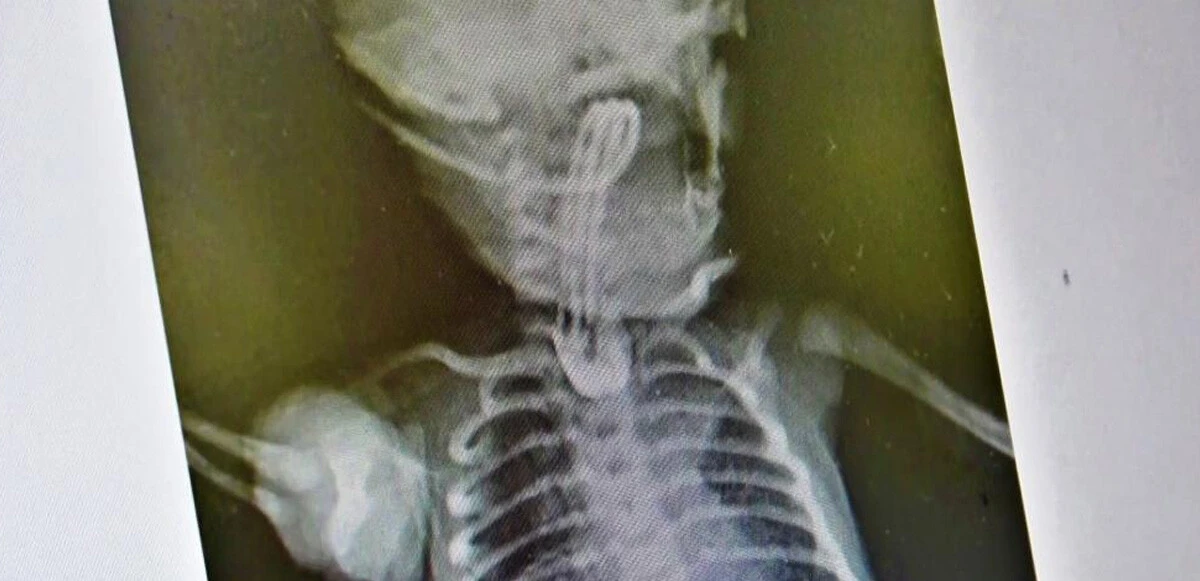

Bebeğin tedavisi hakkında bilgi veren Uzm. Dr. Edirne, “Bebeğimiz doğduğunda yapılan ön tetkiklerde yemek borusunun olmadığı anlaşıldı. 2-3 günlük olduktan sonra ameliyatını gerçekleştirdik. 15 gün sonrasında da ağızdan beslemeye başladık. Yemek borusunun oluştuğunu çekilen filmlerde tetkik ettik. Sonrasında da ailesinin yanına verdik. Kontrolleri yapıldığında ise hiçbir problemi olmadığı görüldü. Eğer bu hastalık tespit edildiğinde zamanında tedavi edilmezse yemek borusu olmadığı için bebeğin beslenme şansı olmuyor. Ondan sonra da maalesef yaşama şansı olmuyor" ifadelerini kullandı.

ameliyat edildi: Doktordan hayati dokunuş" />

Acil tedavi edilmesi gereken bir hastalık olduğunu belirten Edirne, "Öncelikle ultrason ve ön tetkikler yapılıyor. Bütün hazırlıklar yapıldıktan sonra özellikle yeni doğan yoğun bakımın olduğu bir donanımlı bir hastanede bakımının yapılması gerekiyor. Ameliyat da başarılı geçtiği takdirde bu şekilde doğan bebekler hayata tutunuyorlar. Ameliyat yapılmazsa yaşama şansı olmayan bir hastalıktır. Binde bir ihtimalle karşımıza çıkıyor” dedi.